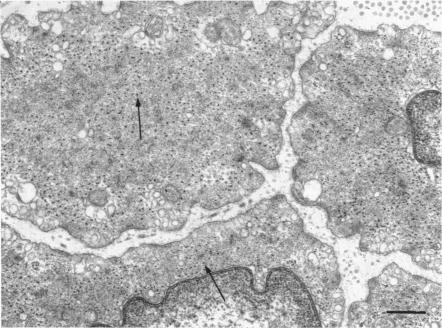

1. The water content, extracellular ((60)CoEDTA) space, ionic composition and ultrastructure of several mammalian smooth muscles were studied after incubation in solutions of varying ionic compositions and osmolarities.2. Substitution of KCl for NaCl resulted in an increase in cell water, K and Cl, accompanied by little change in total wet weight. This was due to a reduction in the extracellular space.3. Changes in extracellular osmolarity produced a wider range of cell volumes in high KCl solutions than in Krebs. The addition of 29-58 mM sucrose to high KCl prevented the swelling.4. Electron microscopy of smooth muscle swollen in high KCl solution revealed light (less electron opaque than normal) fibres of increased diameter, reduction in extracellular space, and nuclear swelling. The normal thick filament lattice was destroyed in swollen, osmium-fixed smooth muscles.5. The ultrastructural changes ascribed to swelling were absent in smooth muscles, (a) depolarized in high K(2)SO(4) solutions, (b) in high KCl solutions with 29-58 mM sucrose, and (c) returned to normal Krebs solution for recovery from swelling.6. Smooth muscles incubated in high KCl (swollen) and high K(2)SO(4) (unswollen) exhibited similar contractile responses, suggesting the filament lattice was intact until fixation, and that the contractile mechanism can operate over a relatively wide range of actin to myosin separations.7. Shrinkage of smooth muscles in high KCl solutions made hypertonic with the addition of 10% sucrose was accompanied by an aggregation of the thick filaments.8. The cell water of fixed taenia coli was reduced (a) by incubation in hypertonic solution followed by fixation in normal glutaraldehyde, or (b) by fixation of normal tissue in hypertonic glutaraldehyde. Osmotic responses during aldehyde fixation may be a source of artifact in the visualization of the normal filament lattice.

4. 在高KCl溶液中肿胀的平滑肌的电子显微镜检查显示,纤维变亮(电子密度低于正常)、直径增加、细胞外空间减少和核肿胀。在肿胀的、经锇固定的平滑肌中,正常的粗肌丝晶格被破坏。

5. 在平滑肌中未观察到归因于肿胀的超微结构变化,(a)在高K₂SO₄溶液中去极化,(b)在含有29 - 58 mM蔗糖的高KCl溶液中,以及(c)恢复到正常Krebs溶液中从肿胀状态恢复。